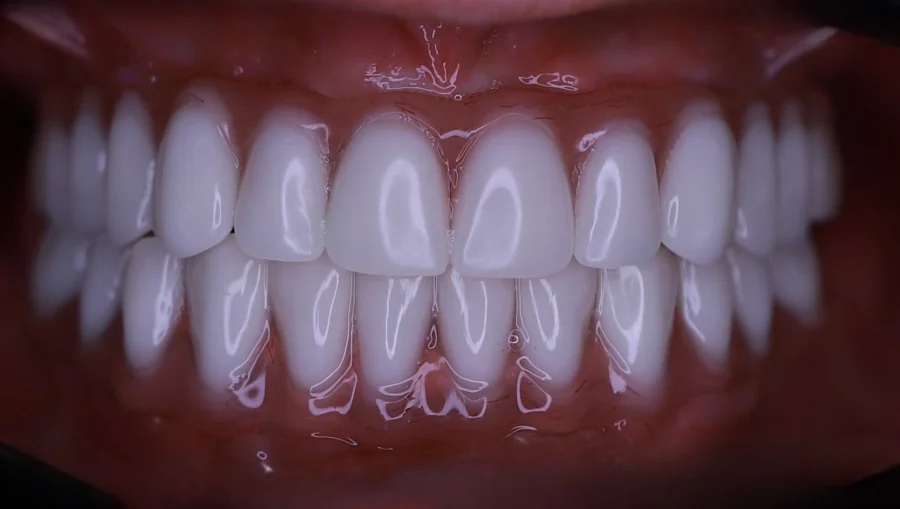

Die Patientin stellte sich mit fortgeschrittener Parodontitis und stark abgenutzten Zähnen durch Bruxismus vor. Sie wünschte sich wieder schöne Zähne, eine stabile Kaufunktion und ein natürlich wirkendes Lächeln.

Behandlungsmaßnahmen: Laserunterstützte Zahnreinigung bei Parodontitis, Setzen von 5 Zahnimplantaten in den Seitenbereichen von Ober- und Unterkiefer, Bruxismus-Therapie mit Botulinumtoxin sowie Zahnkronen in beiden Kiefern. Die Vollkeramik-Zahnkrone Vorher Nachher Bilder zeigen die deutliche Verbesserung von Funktion, Ästhetik und Komfort.